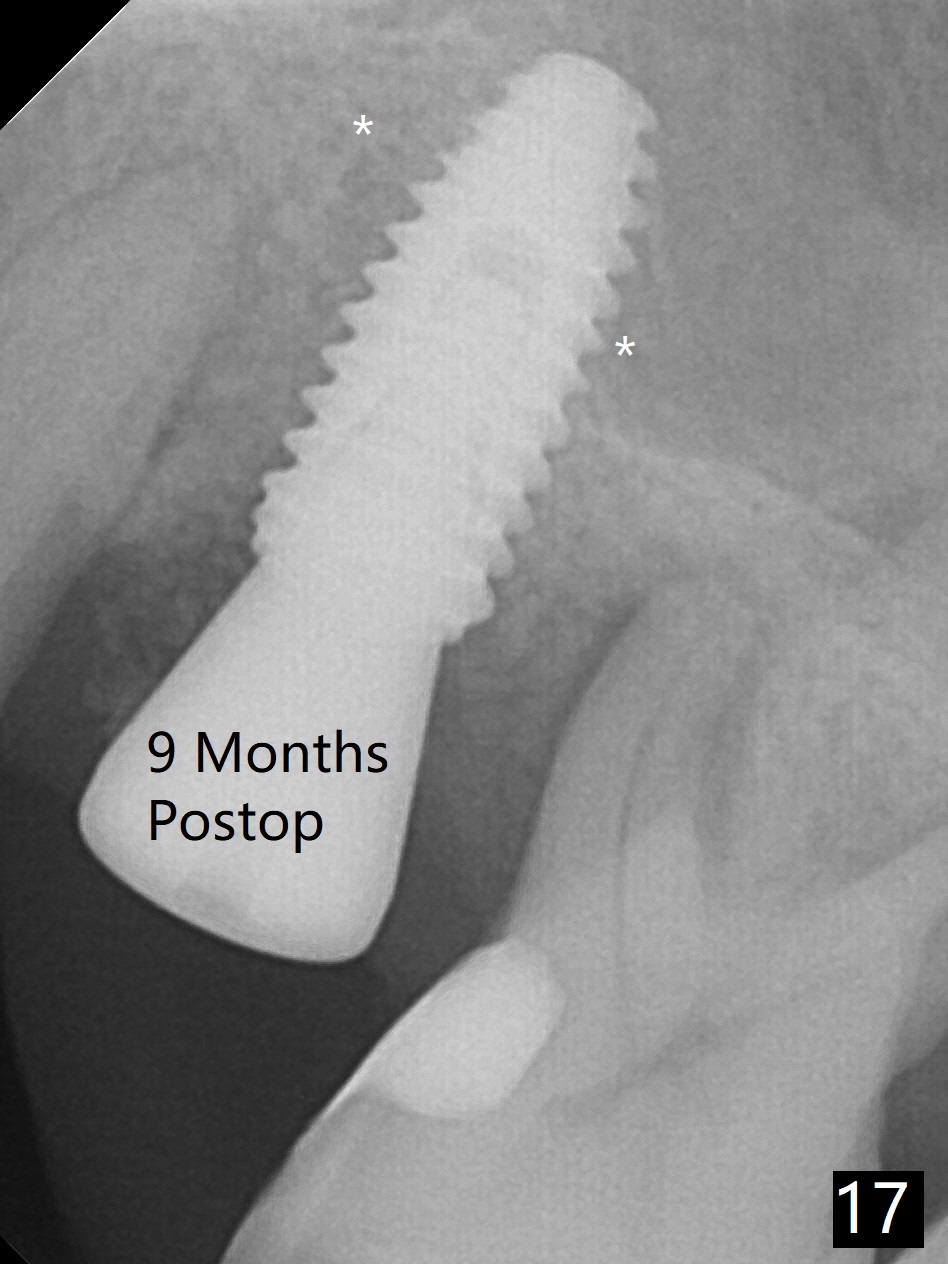

When the initial osteotomy is off substantially (Fig.4), an osteotomy should be established de novo and as early as possible (Fig.14) so that subsequent osteotomy will not relapse to a great extent. More ideally, the initial osteotomy should be planned correctly (Fig.15,16) with sacrifice of the bone height. Nearly 1 month postop, the 4.5x5.5(5) cementation abutment is loose. When it is removed, the patient feels pain from the implant. A 5.5x6 mm healing abutment is placed instead. The implant osteointegrates with trabecular pattern in the sinus 9 months postop (Fig.20 *). The gingiva around the crown at #13 is healthy 1 year 4 months post cementation (Fig.18). Check the distal surface of #13 for bone loss if the tooth #14 is to be extracted.